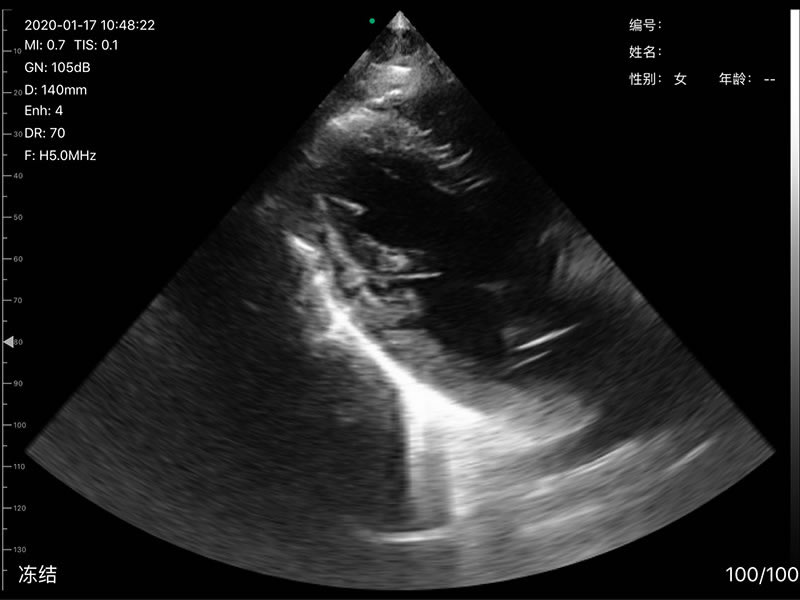

• 探头频率:相控阵2.2/3.6MHz,线阵7.5/10 MHz

• 扫描声头:同时具备微凸、线阵两个声头,并可通过按键快速切换

• 扫描深度:相控阵20-240mm,线阵 20-100mm,可调

• 显示模式:B、B/M、Color、PW、PDI